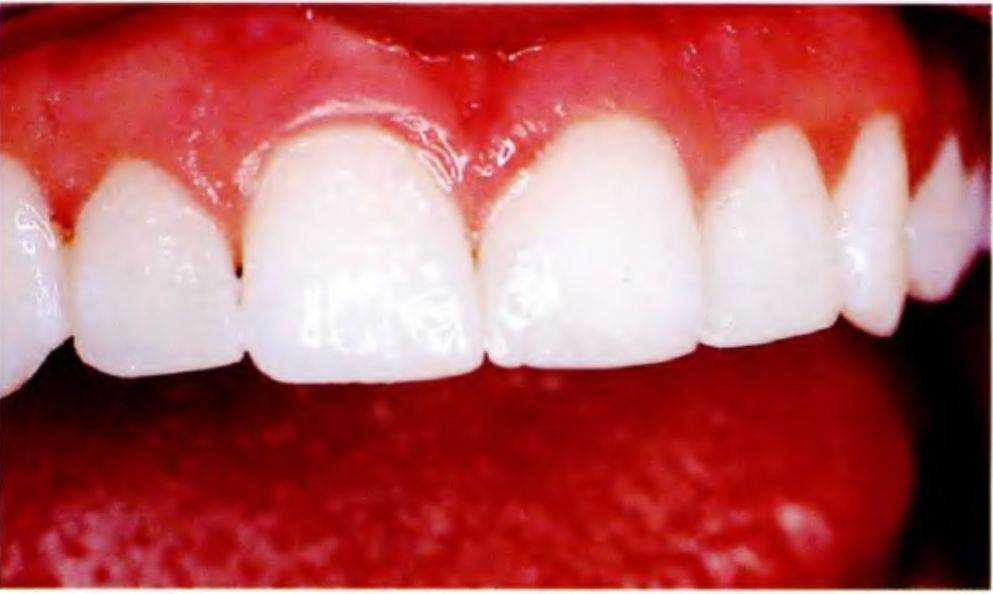

Мать 14-летней девочки обратилась в стоматологическую клинику после завершения ее ортодонтического лечения. Основное пожелание касалось устранения пространств между передними зубами верхней челюсти (рис. с 6-12с по 6-12е). Ортодонт опре-

Рис. 6-12с. Портретная фотография 14-летней пациентки

делил, что верхние зубы слишком узкие, поэтому устранение этих пространств ортодонтическими методами будет невозможно, и направил пациентку для проведения реставрационного лечения.

Стоматологическое обследование подтвердило мнение ортодонта. Межзубные пространства в переднем отделе верхней челюсти были слишком широкими, боковые резцы повернуты вокруг своей оси. Мать девочки предпочла адгезивные реставрации для максимального сохранения тканей зубов.